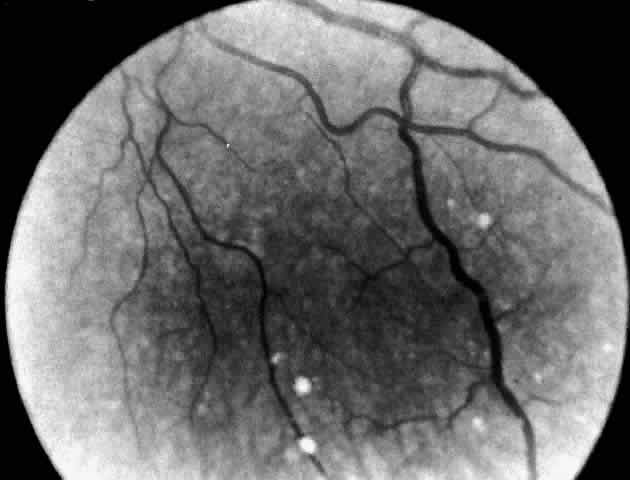

| Gaucher's disease is an autosomal recessive sphingolipidosis. The

system. The disease, first described by Gaucher in 1882,72 is characterized by hepatosplenomegaly and the presence of lipid-laden storage cells called Gaucher's cells in the bone marrow and organs. The disease is panethnic, although Gaucher's disease type I has a high prevalence among Ashkenazi Jews. A subset of' Gaucher's disease type III has been described with a high incidence in a Swedish isolate.73 CLINICAL MANIFESTATIONS. Three types of Gaucher's disease are distinguished: type II acute infantile neuronopathic, type III subacute juvenile neuronopathic, and type I chronic adult non-neuronopathic.74 Type II acute infantile neuronopathic Gaucher's disease is a unique neurovisceral disorder. Clinically it simulates infantile Niemann-Pick disease with the insidious onset of symptoms in early infancy, including failure to thrive, progressive hepatosplenomegaly, laryngeal stridor, and dysphagia. Anemia, thrombocytopenia, and leukopenia are present. Every infant with type II Gaucher's disease has evidence of severe and progressive CNS dysfunction before death. Signs of neurologic deterioration usually appear before 6 months and frequently before 3 months of age. A rather stereotyped neurologic syndrome has been observed in which hypotonia gives way to spastic weakness associated with a persistent retroflexion of the neck, with internal strabismus, seizures, and signs of pseudobulbar palsy. Motor skills and mental awareness are rapidly lost. The usual cause of death as the bulbar palsy worsens is bronchial aspiration and pneumonia. Type III subacute juvenile neuronopathic Gaucher's disease describes children and young adults who do not fit into either of the other two groups and whose illness is complicated by neurologic manifestations that differ from, and have a later age at onset and more chronic course than, those of the infantile form. Two clinical pictures are distinguished, depending on the age at onset of neurologic symptoms. The older patients,75–77 including two patients reported by Winkelman and co-workers,78 in whom symptoms began in late childhood, adolescence, or' early adult years, presented with similar neurologic syndromes, consisting of myoclonic epilepsy and supranuclear disorders of gaze. In some,75 including Winkelman's second patient,76 the gaze disorder was the more prominent; in others,76 myoclonic epilepsy was the most evident feature. Freedom from signs of cerebral involvement is the sine qua non for the diagnosis of type I chronic adult non-neuronopathic Gaucher's disease. Patients with this variant can have onset of the disease in childhood or in adulthood and a prolonged course. They manifest hepatosplenomegaly, anemia, thrombocytopenia, periods of bleeding, and pathologic bone fractures. Radiographic abnormalities of bone are present in 50% to 75% of patients. The most common sign is an Erlenmeyer flask deformity at the lower end of the femur due to expansion of the marrow cavity. OCULAR MANIFESTATIONS. The validity of two cited cases79,80 of a cherry-red spot in the retina of patients with Gaucher's disease has been questioned by Cogan and colleagues.81 In addition, one reported case of macular cherry-red spots in a 20-year-old woman believed to have Gaucher's disease, along with other similar cases, in retrospect now seems to have been an example of the cherry-red spot-myoclonus syndrome of sialidase deficiency.82,83 All three suspected Gaucher's disease cases antedated the biochemical means for establishing the diagnosis. In fact, it was not until 1965 that the enzyme assay for Gaucher's disease became available. To determine for certain the incidence of macular cherry-red spots in Gaucher's disease, Cogan and colleagues81 examined 42 enzymatically proven cases of the disease and reviewed the records of 9 others. In none was a cherry-red spot seen. In three patients with type III subacute juvenile neuronopathic Gaucher's disease however, the retina showed a unique retinopathy. The findings in Cogan's case 1 are described: “Both fundi showed discrete white spots randomly distributed in the posterior fundus, especially along the inferior vascular arcades (Fig. 8). The spots varied in diameter from just visible to approximately 0.1 mm and were situated in the superficial retina or on the surface of the retina. Several covered the retinal vessels. The disc and retinal vessels were normal.” The child, an 11-year-old boy, had normal acuity and a full field of vision by confrontation. He had presented at age 3 years with splenomegaly. Normal vision and similar retinal abnormalities were observed in a mildly mentally retarded 18-year-old woman (case 2) presenting with splenomegaly at age 1 year and in a 6½-year-old boy (case 3) noted to have hepatosplenomegaly in the first year of life. The patients in cases 1 and 3 had conspicuous supranuclear defects of eye movement. Japanese observers Yanagida, Matsumoto, Tokudo, and Hirose were the first to report the peculiar retinal spots in type III juvenile Gaucher's disease between 1950 and 1965. Their clinical reports in Japanese journals are referenced in Cogan and colleagues' paper.81 Type III juvenile neuronopathic Gaucher's disease is also associated with a distinctive supranuclear eye movement disorder affecting primarily horizontal gaze and only occasionally vertical gaze.75–78,84,85 The early defect in horizontal gaze involves the saccadic system, and the disorder mimics closely congenital ocular motor apraxia. To distinguish Gaucher's disease cases from benign congenital apraxia, it is essential to obtain the appropriate enzyme studies. NEUROPATHOLOGY. The liver, spleen, and long bones are the primary organs affected by the storage of glucosylceramide. The dominating precursors to the accumulation of glucosylceramide are derived from the normal turnover of leukocytes and erythrocytes, but other tissue cells also contribute. The highly cytotoxic substance glucosylsphingosine (the non-acyl derivative of glucosylceramide) is also stored in excess in the viscera in all types of Gaucher's disease and in the brain in the neuronopathic types, type II and III. This accumulation leads to cell death. Like the clinical features, the neuropathologic changes in patients with type II infantile neuronopathic Gaucher's disease are quite uniform. Nerve cell loss and neuronophagia involving the brain stem and deep cerebellar nuclei predominate, but the thalamus, basal ganglia, and spinal cord are also affected. Such neuronal destruction is diffuse and, except for oculomotor abnormalities and dysphagia, causes no localizing signs. Perivascular nodular collections of Gaucher's cells are found in the brain, invading the meninges and in Virchow Robin spaces. Gaucher's cells have a unique appearance. The cytoplasm has a wrinkled tissue-paper appearance because of interwoven fibrils contained within it. Under the electron microscope the cells contain large lysosomes filled with tubular profiles. These cells are distinct in their appearance and differ markedly from foam cells seen in other lipidoses.86 A pathologic study of two siblings with neuronopathic Gaucher disease and supranuclear upgaze and horizontal gaze palsies has demonstrated similar widespread involvement of the cortex, cerebellum, and spinal cord. The midbrain, pretectal region, oculomotor and red nuclei, superior colliculus, substantia nigra, and reticular formation were all involved. In the pons, the paramedian reticular formation showed pathologic change, as did the abducens and superior vestibular nuclei.78 An electron microscopic study of Gaucher's cells in the eye in type III juvenile neuronopathic disease is reported from Japan by Ueno and associates87,88 who noted white spots in an arcuate pattern in the fundi of an 8-year-old Japanese boy. At autopsy the retinal spots corresponded to polymorphonuclear giant cells within and on the surface of the retina. These cells were large and stained positively for glycolipid and acid phosphatase. DIAGNOSTIC TESTS. The disease is confirmed by demonstration of a deficiency of glucocerebroside-ß-glucosidase in leukocytes and fibroblasts. In spite of the range of biologic expression, the same enzyme is deficient in all three types of the disease. Moreover, lack of complementation in cell fusion studies strongly suggests that these forms of Gaucher's disease represent allelic mutations at the same gene locus.89 There is a rare variant of Gaucher's disease clinically similar to adult non-neuronopathic disease type I but in which glucocerebroside-ß-glucosidase activity is normal. In this variant the defect is believed to be due to absence of the A activator protein.90 Prenatal diagnosis is available for all three types. It is seldom requested for type I Gaucher's disease. |